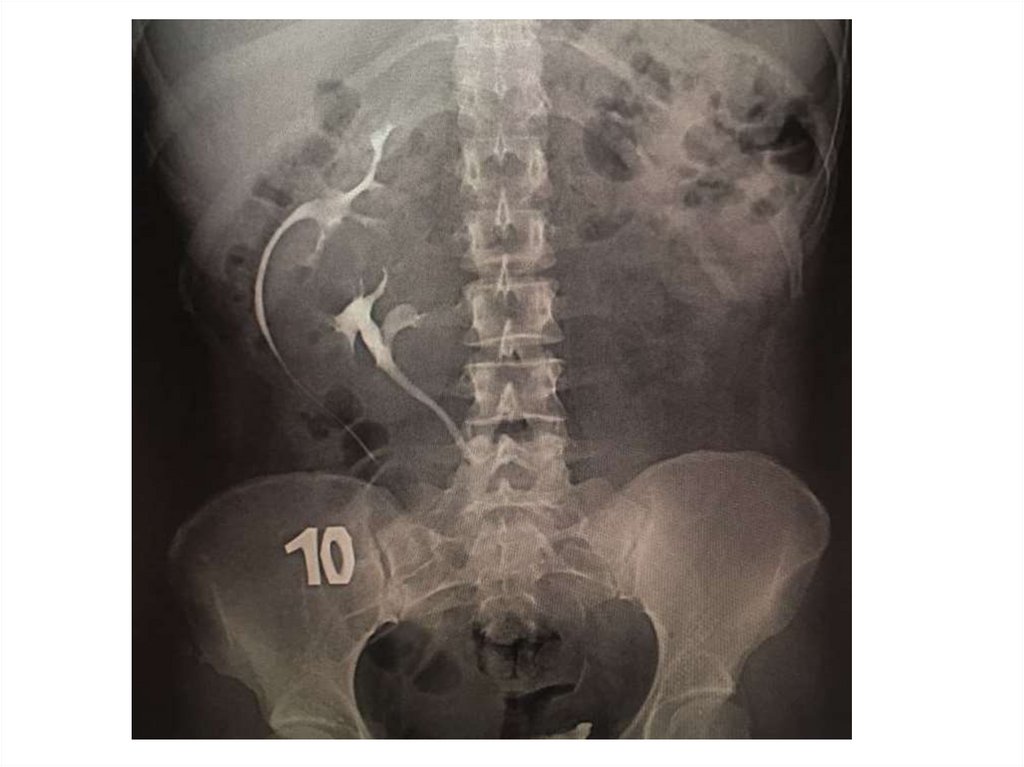

Назовите

• Вид исследования

• Область исследования

• Патологию